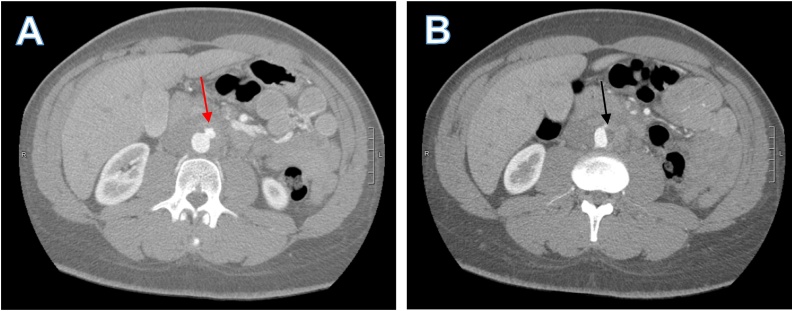

A 36-year-old man with well controlled HIV, on abacavir-lamivudine-dolutegravir (CD4 count of 931 cells/μL with undetectable viral load), presented with a one-week history of lower abdominal pain radiating to his back. He initially attributed the pain to constipation but when the pain progressed, he decided to seek medical advice at a local emergency room. CT scan of the abdomen and pelvis with oral and intravenous contrast showed an ill-defined infrarenal periaortic mass with an adjacent eccentric thrombus in the abdominal aorta and subtle enhancement of the vasa vasorum concerning for focal aortitis (Fig. 1). Initial concern was for a neoplastic process and outpatient CT guided biopsy was scheduled, but symptoms intensified over ten days prompting further medical evaluation. CT angiogram of the chest and abdomen showed a pseudoaneurysm of the aorta (Fig. 2A) and a focal dissection extending to the aortic bifurcation (Fig. 2B). Given these findings, the patient was transferred to our tertiary care center for further surgical and medical management.

Fig. 2.

Axial views of CT angiogram of the abdomen. A) Pseudoaneurysm from the anterior left aspect of the aorta (red arrow) measuring about 1.2 cm. B) Flattening of left aortic border and non-enhancing short segment of the left side of the aorta representing a small focal dissection that extended to aortic bifurcation (Black arrow). (For interpretation of the references to colour in this Figure legend, the reader is referred to the web version of this article).

C. fetus aortitis characteristically has rapid progression to aneurysm formation and subsequently, to aortic rupture. Overall mortality of C. fetus aortitis is 20–30 % but mortality approaches 100 % if rupture occurs before surgical intervention can be conducted [[10], [11], [12]]. Our case illustrates the rapid progression of C. fetus from focal aortitis (Fig. 1) to the development of pseudoaneurysm over ten days (Fig. 2). Once the pseudoaneurysm was identified, emergent open resection and neo-aortoiliac replacement with his left femoral vein was conducted. This case reinforces the need for a high index of suspicion to identify and surgically treat C. fetus aortitis, thereby preventing progression to aortic rupture and reducing mortality.